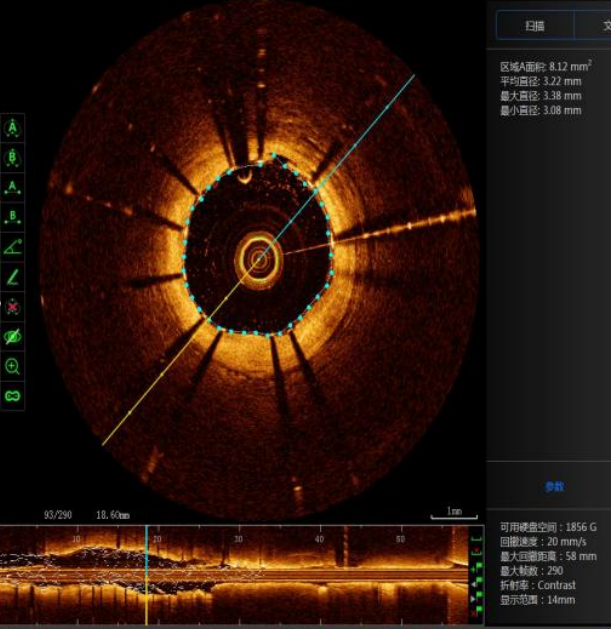

【关注】首例开展,西南医大中医院再创新高!

西南医科大学附属中医院成功开展医院首例新一代国产光学相干断层(OCT)检查指导下冠状动脉支架精准植入术近日,55岁的王先生因活动后心累、气促、头痛等症状,来到西南医科大学附属中医医院治疗,心血管内科医生接诊后为王先生完善了相关检查,找到了病...